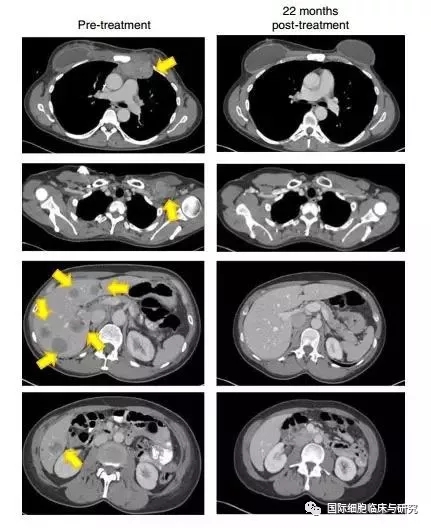

一名难治性激素阳性转移性乳腺癌患者接受了4种突变蛋白(SLC3A2,KIAA0368,CADPS2和CTSB)的TILs,治疗22个月后,患者肿瘤完全消失,且4年后仍未出现进展或复发。这一案例发表在2018年《自然医学》(Nature Medicine)杂志上。